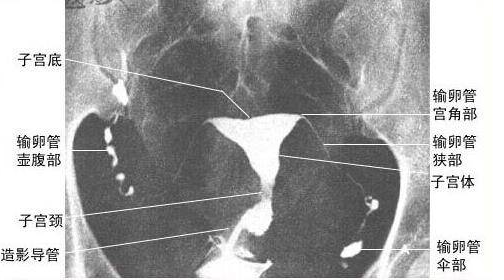

輸卵管位于子宮的兩側,為一對細長而彎曲的肌性管道,為卵子與精子結合場所及運送受精卵的通道,內側與子宮角相連通,開口于子宮腔,稱為輸卵管子宮口,外端游離呈傘狀,開口于腹膜腔,稱為輸卵管腹腔口,全長8~14cm。輸卵管游離的傘部呈漏斗狀,漏斗周緣有許多指狀突起稱輸卵管傘,有[拾卵]作用。